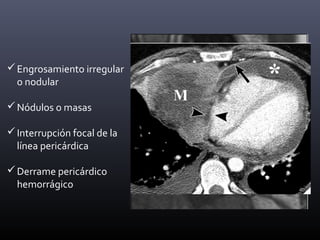

Engrosamiento irregular

o nodular

Nódulos o masas

Interrupción focal de la

línea pericárdica

Derrame pericárdico

hemorrágico